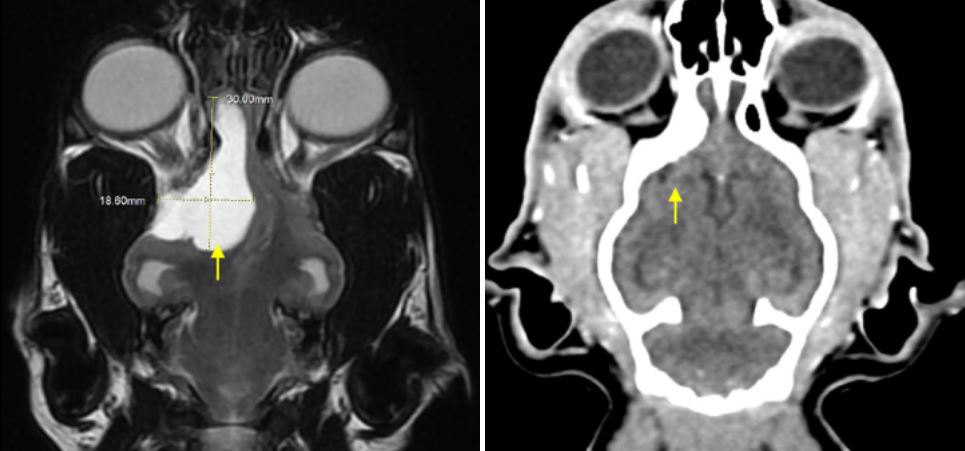

수술 9개월 후 재발 여부를 확인하기 위해 CT를 통한 추적 검사 실시했을 때, 종괴가 있던 부위는 정상 뇌조직이 자리잡고 있었으며, 현재까지 경련과 같은 임상 증상이 재발되지 않고 잘 지내고 있습니다.

<좌: 수술 전 ㅣ 우: 수술 후>